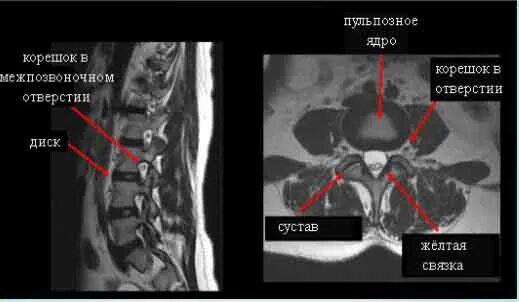

Мрт при боли в суставах